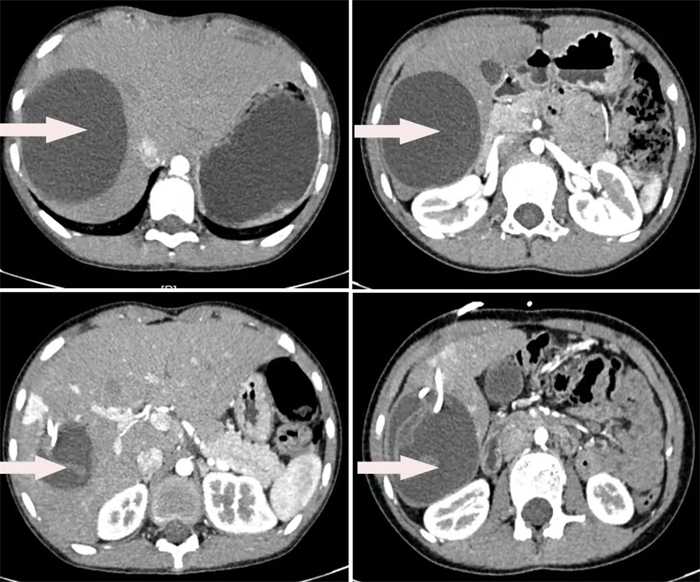

患者2,10歲女性,因“發(fā)現(xiàn)肝臟包塊4天” 入院,經(jīng)CT檢查提示肝右葉占位性病變,考慮肝細粒棘球蚴病。